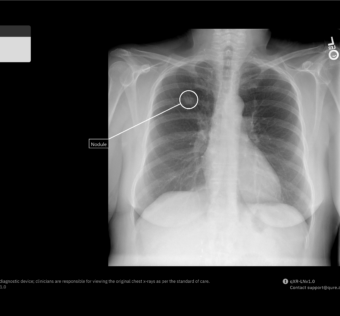

Merck Global Health Innovation Fund Invests in Qure.ai to Expand Lung Cancer DetectionHIT Consultant - (Tuesday June 25, 2024) - AI/ Digital Health/ Frequent Updates/ HIT Consultant | |

![]() | What You Should Know: – Merck Global Health Innovation Fund (MGHIF), a leader in healthcare impact investing, announced a strategic investment in Qure.ai, a prominent developer of artificial intelligence (AI) solutions for medical imaging. – The... #MerckGlobalHealthInnovationFund Invests in Qure.ai to Expand Lung Cancer Detection#Investment Details: Merck Global Health Innovation Fund has recently invested in Qure.ai to enhance lung cancer detection using AI technology. This investment aims to improve early diagnosis and treatment outcomes for patients.#Qure.ai's AI Technology: Qure.ai utilizes advanced AI technology to analyze medical imaging data and detect lung cancer at an early stage. The technology enables faster and more accurate diagnosis, leading to improved patient outcomes.#Impact on Healthcare IT: This investment highlights the growing importance of AI technology in healthcare IT, particularly in the field of cancer detection. By leveraging AI algorithms, healthcare providers can enhance diagnostic accuracy and efficiency, ultimately improving patient care. As a healthcare IT expert, write a 50-80 extractive summarization summary for social media platforms, that is focused, accurate, and strictly reflects the content based on a blog post from the given URL. The summary should include all headings from the blog post, with inline hashtags for each heading. When including the inline hashtags, use specific hashtags related to the headings rather than generic healthcare or technology hashtags. If the headings in the blog post are too long or unclear, feel free to rephrase them into shorter, clearer versions that still convey the main idea. The target audience is other healthcare IT professionals.Following is the title and url. Merck Global Health Innovation Fund Invests in Qure.ai to Expand Lung Cancer Detection https://hitconsultant.net/2024/06/25/merck-global-health-innovation-fund-invests-in-qure-ai-to-expand-lung-cancer-detection/ { "id": "chatcmpl-9eAzcadimOcwaY0VtLdZJGme6HqBJ", "object": "chat.completion", "created": 1719362404, "model": "gpt-3.5-turbo-0125", "choices": [ { "index": 0, "message": { "role": "assistant", "content": "#MerckGlobalHealthInnovationFund Invests in Qure.ai to Expand Lung Cancer Detectionnn#Investment Details:nMerck Global Health Innovation Fund has recently invested in Qure.ai to enhance lung cancer detection using AI technology. This investment aims to improve early diagnosis and treatment outcomes for patients.nn#Qure.ai's AI Technology:nQure.ai utilizes advanced AI technology to analyze medical imaging data and detect lung cancer at an early stage. The technology enables faster and more accurate diagnosis, leading to improved patient outcomes.nn#Impact on Healthcare IT:nThis investment highlights the growing importance of AI technology in healthcare IT, particularly in the field of cancer detection. By leveraging AI algorithms, healthcare providers can enhance diagnostic accuracy and efficiency, ultimately improving patient care.nn" }, "logprobs": null, "finish_reason": "length" } ], "usage": { "prompt_tokens": 193, "completion_tokens": 150, "total_tokens": 343 }, "system_fingerprint": null } Prompt Tokens - 193 |